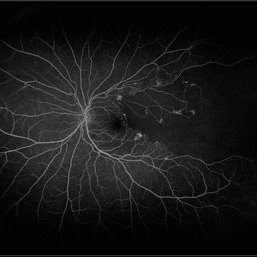

Coats Disease

Composite fluorescein angiogram of the left eye of a man with Coats Disease.

Photographer: Olivia Rainey

Imaging device: Heidelberg Spectralis

Condition/keywords: Coats' disease, composite, fluorescein angiogram (FA), fluorescein leakage, Heidelburg Spectralis